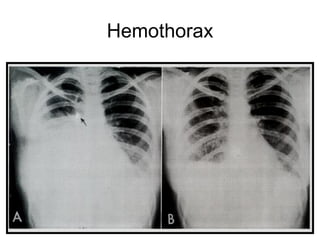

Hemothorax